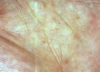

bowen disease

intra-epidermal carcinoma in situ (no dermal invasion), which can rarely become invasive

thought to be due to long term sun exposure, presents on exposed skin (most commonly womens legs)

epidermal neoplastic lesions that cannot yet invade the underlying tissues

bowens disease features

erythematous scaly patches/plaques with an irregular border

can mimic inflammatory conditions

lesions do not clear but slowly increase in size with time